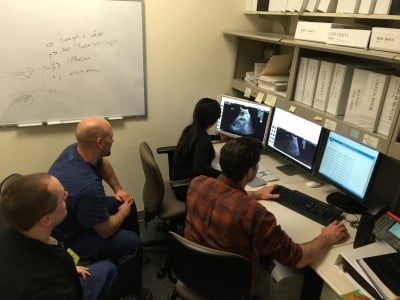

Fellow participation in the maintenance of our home grown QA workflow solution as well as participation in Image Review, which occurs every day Monday – Friday provides a unique experience for fellows.

Image Review format varies to provide a breadth of experience and promote fellow and resident education. The Ultrasound Fellow gets 1:1 dedicated image review time with fellowship director and experienced faculty, but also has the opportunity to lead image review sessions for residents/medical students.